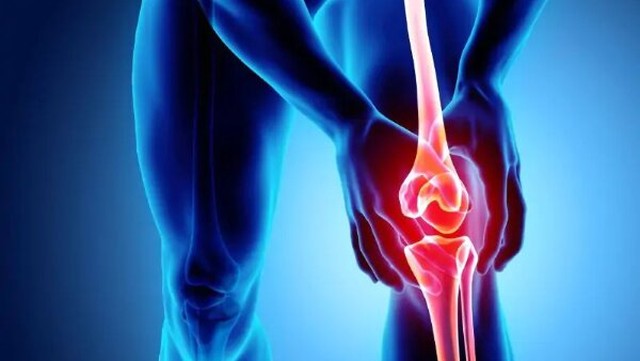

:format(webp)/quy_trinh_thuc_hien_hut_dich_khop_goi_8fccb2c938.jpg)

Đối với bệnh nhân gặp vấn đề ở khớp gối thường xuyên, bác sĩ có thể đề xuất thực hiện thủ thuật hút dịch khớp gối, một phương pháp đơn giản và hiệu quả. Nhưng không phải ai cũng hiểu rõ về tính chất và các ưu, nhược điểm của quy trình này.